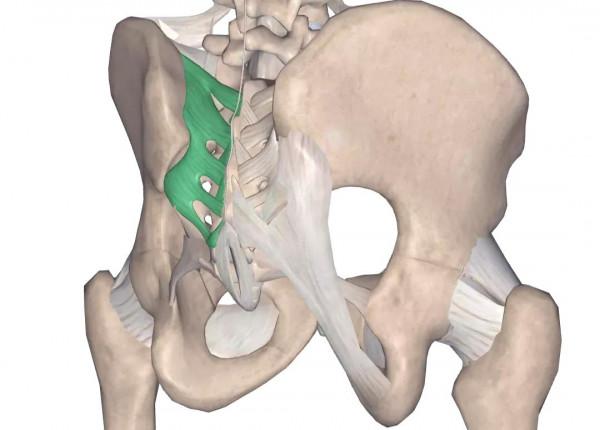

骶髂關節由兩塊髂骨與一塊骶骨構成。關節面扁平,彼此對合非常緊密,屬平面關節。關節囊緊張,緊貼於關節面周緣,其周圍有許多強韌的韌帶加強,關節腔狹小,呈裂隙狀。

骶髂關節是骨盆環三個關節中的主要部分,是脊柱與下肢間聯絡的樞紐,該關節活動度小,但其承受上半身的全部重量,為力量的緩衝帶。